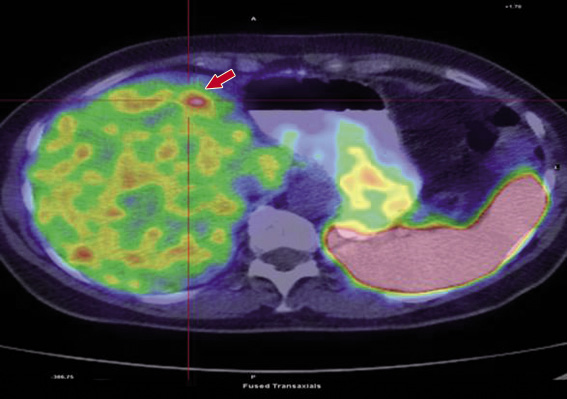

Figura 1. Immagine PET-TC rilevata nella paziente nel gennaio 2008: recidiva di malattia a livello del III segmento epatico. La freccia indica la lesione epatica

Nel sospetto che la lesione epatica sia di natura metastatica, la paziente viene sottoposta a ulteriori indagini: clisma del tenue, pancolonscopia e ultrasonografiaendoscopica (EUS), che permettono di esplorare le vie digestive superiori, inferiori e il pancreas. Tali indagini risultano tutte negative. La PET con fluorodesossiglucosio (FDG) risulta negativa, la PET con 68Gallio, che rileva le lesioni che esprimono i recettori per la somatostatina, evidenzia la sola lesione epatica. Negativi risultano i marker per neoplasie del tratto digerente (CEA, CA 19-9) e genitale (CA 125).

Nel gennaio 2008 si evidenzia la presenza di una formazione di 2,7 cm a livello del III segmento epatico, confermata anche da una PET con gallio (Figura 1).